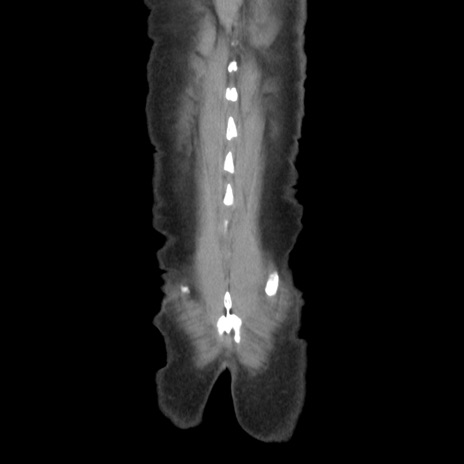

症例37(冠状断像)

【症例】40歳代 男性

【主訴】腹痛

【現病歴】4時間ほど前に電車に乗車中に臍部上より腹痛出現。徐々に増悪し起立困難となり、救急外来受診。生ものは数日食べていない。今朝お雑煮を食べた。

【身体所見】BT 36.8℃、BP 117/84mmHg、HR 91/min、SpO2 97%、苦悶様、腹部:臍上部広範囲圧痛あり、反跳痛±

【データ】WBC 8100、CRP 0.03